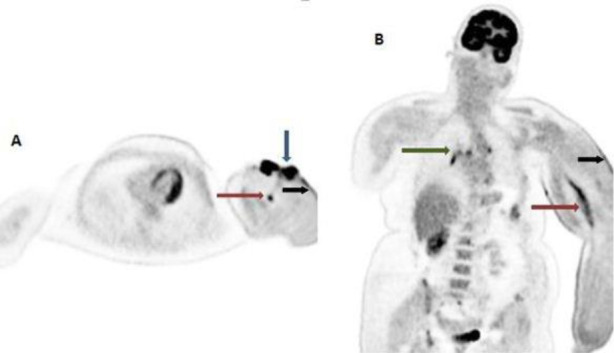

Objectives: Lymphangiosarcoma is a rare tumor that affects the upper limbs of patients who have undergone breast cancer surgery, including axillary dissection, followed by radiation therapy (RT) to the axilla and has a poor prognosis. 18F-FDG PET/CT may enable the earlier detection of malignant transformation in a setting of chronic lymphedema and help evaluate the extent and staging of the tumor, allowing earlier initiation of treatment options.

Case presentation: We herein report a case of cutaneous lymphangiosarcoma in a 47-year-old breast carcinoma patient, which occurred 9 years after initial surgery and radiation therapy. Distant metastases were detected on 18F-FDG PET/CT. The patient underwent fore-quarter amputation of the upper limb and concurrent chemo-radiation therapy. However, she succumbed to her disease after 3 cycles of chemotherapy.

Conclusions: 18F-FDG PET/CT scan helps in the early detection of malignant transformation and lymphangiosarcoma in a setting of chronic lymphedema in breast carcinoma patients following radiation therapy to the axilla. Furthermore, it helps determine the extent of regional spread and detect metastatic involvement, thus enabling better clinical management of these patients.